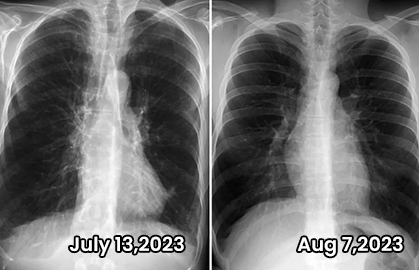

After years of on and off smoking and vaping I decided to quit! So I got this to help clear out some of the gunk in my lungs! Has it helped?YES! After using Sheenice for just one month, I went to the hospital for a checkup, and the doctor told me that my emphysema had disappeared.  It can be really difficult to find good quality organic products like this one that are affordable! Highly recommend!